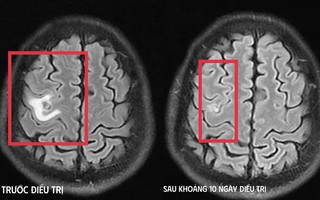

Co giật do sán não suýt nhầm lẫn với u não

(NLĐO) - Tổn thương não do sán khiến bệnh nhân co giật, đau đầu nhẹ - triệu chứng mờ nhạt nhưng dễ bị bỏ sót.